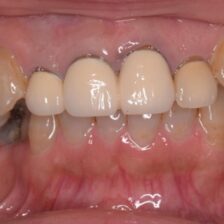

精密根管治療により、

歯を残せる可能性を最大限に

当院ではCT・マイクロスコープ・セファロなどの精密検査機器を活用し、歯を残すための選択肢をできる限りご提案します。

歯髄温存治療(MTA)や歯冠長延長術、矯正的挺出など、専門的な治療にも対応。